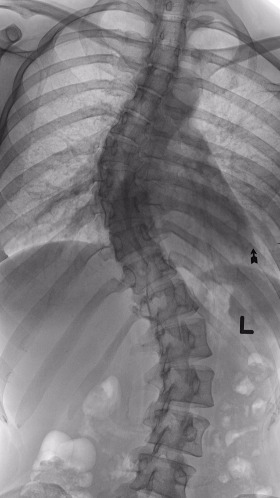

우리나라뿐 아니라 전 세계적으로 우사인 볼트에 대한 많은 이야기들과 그에 대한 기사, 분석 글들이 연일 쏟아진다. 또한 우사인 볼트가 척추 측만 Scoliosis을 가지고 있다는 이야기는 이제 누구나 알고 있는 사실이다.

척추 측만은 선천적으로나 후천적으로 우리의 척추가 S 자형이나 C 자형으로 휘어진 상태를 말하고,

불균형한 골반과 비대칭적인 허리라인으로 인해 심한 경우에는 허리 통증은 물론 장기 압박까지도 올 수 있는 척추의 비정상적인 정렬 상태를 의미한다.